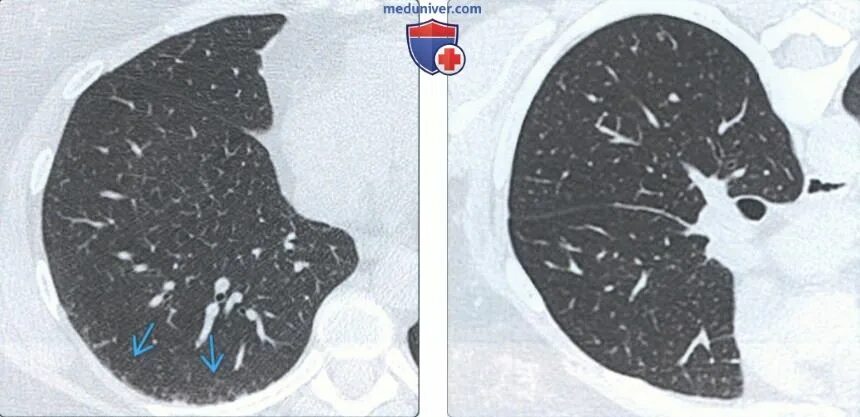

Гипостатические изменения кт